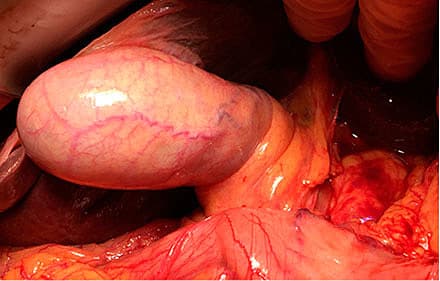

Galdesten tabes oftest i forbindelse med iatrogen galdeblæreperforation under LK [2]. Studier viser, at incidensen for perforation af galdeblæren under LK er 2-40% og for tab af galdesten 1-40% [2, 6, 7, 11]. En konkret incidens for galdeblæreperforation og tab af galdesten kan være vanskelig at fastslå: Dels kan det være svært at observere tab af galdesten pga. indskrænket synsfelt og begrænset mulighed for mobilisering af hepar og tilstødende organer, og dels kan der være utilstrækkelige operationsbeskrivelser, hvor peroperativt tab af galdesten eller mistanke herom ekskluderes. De kirurgiske omstændigheder kan samtidig besværliggøre laparoskopisk fjernelse af de tabte sten [2].

I et retrospektivt studie sammenfattes tre afgørende risikofaktorer, der disponerer for iatrogen galdeblæreperforation: 1) kronisk kolecystitis med fortykket væg > 7 mm detekteret på en præoperativ ultralyd (UL)-skanning, 2) svært dilateret galdeblære (> 8 × 4 × 4 cm på en UL-skanning) og 3) tidligere laparotomi. Tilstedeværelsen af alle tre faktorer øger perforationsrisikoen fra 4% til 25% [12]. Derudover er overvægt, høj alder, forekomst af intraabdominale adhærencer samt tilstedeværelsen af pigmentsten påvist at øge perforationsrisikoen [13, 14]. Iatrogen perforation sker oftest ved overbelastning af galdeblærevæggen ifm. mobilisering af galdeblæren (især ved inflammeret eller ødematøs væg), ved dissektion af galdeblæren fra den hepatiske fossa eller ved ekstraktion af galdeblæren gennem porthullet [7, 15, 16]. I et studie af 17 forskellige variable, der har indflydelse på risiko for iatrogen galdeblæreperforation, blev der påvist signifikant korrelation i multivariatanalyse for: 1) mandligt køn, 2) tidligere akut kolecystitis, 3) anvendelse af laser eller diatermi til dissektion og 4) tilstedeværelsen af makroskopisk inflammeret galdeblære [17]. Baseret på forskellige faktorer må en øget risiko for perforation derfor kunne vurderes ud fra de ovennævnte studier.